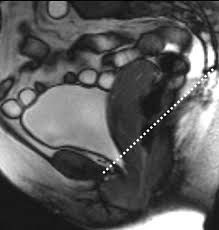

Dashed line corresponds to pubococcygeal line (PCL)

Currently, no universally accepted radiologic criteria for assessing pelvic floor dysfunction exist; however, the most widely accepted criteria involve organ movement below the pubococcygeal line (PCL), which extends from the inferior margin of the symphysis pubis to midway between the frst and second coccygeal segments. A line that extends from the lowermost aspect of the symphysis pubis to the puborectalis muscle forms the puborectalis hiatus. In the normal patient, the puborectalis hiatus is <6 cm and does not descend >2 cm below the PCL. The upper urethra, urethrovesical junction, bladder, upper vagina, uterus, small bowel, sigmoid colon, mesenteric fat, and rectum should all be above the hiatus. Staging of any prolapse is done in 2-cm increments below the puborectalis hiatus. Small is 0 to 2 cm below, moderate is 2 to 4 cm, and a large prolapse extends >4 cm below this line.

For optimal MRI evaluation in the sagittal plane, the patient is placed in the supine position. Static images are frst obtained, with subsequent series of images performed during resting and straining in the midsagittal plane. Selected midline sagittal T2W images at rest and on the Valsalva maneuver and/or sagittal 2D GRE images in real-time at rest and on Valsalva are used to assess the degree of pelvic floor descent and pelvic organ prolapse  Some authors advocate the use of intraluminal contrast, but this is not used routinely at our institution.